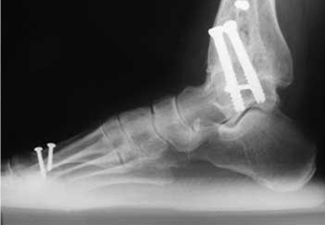

Artrodesis

Uno de los posibles tratamientos quirúrgicos siendo la artrodesis de tobillo. Consiste en la alineación de la deformidad, resección del cartílago y fijación del hueso con distintos tipos de osteosíntesis, lo que dejaba como resultado un tobillo no doloroso, pero rígido.

Se denomina atrodesis a la fijación de la articulación, mediante la resección del cartigalo enfermo y el contacto directo de un hueso con el otro. Generalmente se fija mediante una osteosíntesis con tornillos, placas o fijación externa.

Este es uno de los métodos de tratamiento de la artrosis severa de la articulación del tobillo, y juega con un rol muy importante, ya que nos permite a los cirujanos ortopedistas obtener un pie indoloro, plantigrado y estable.